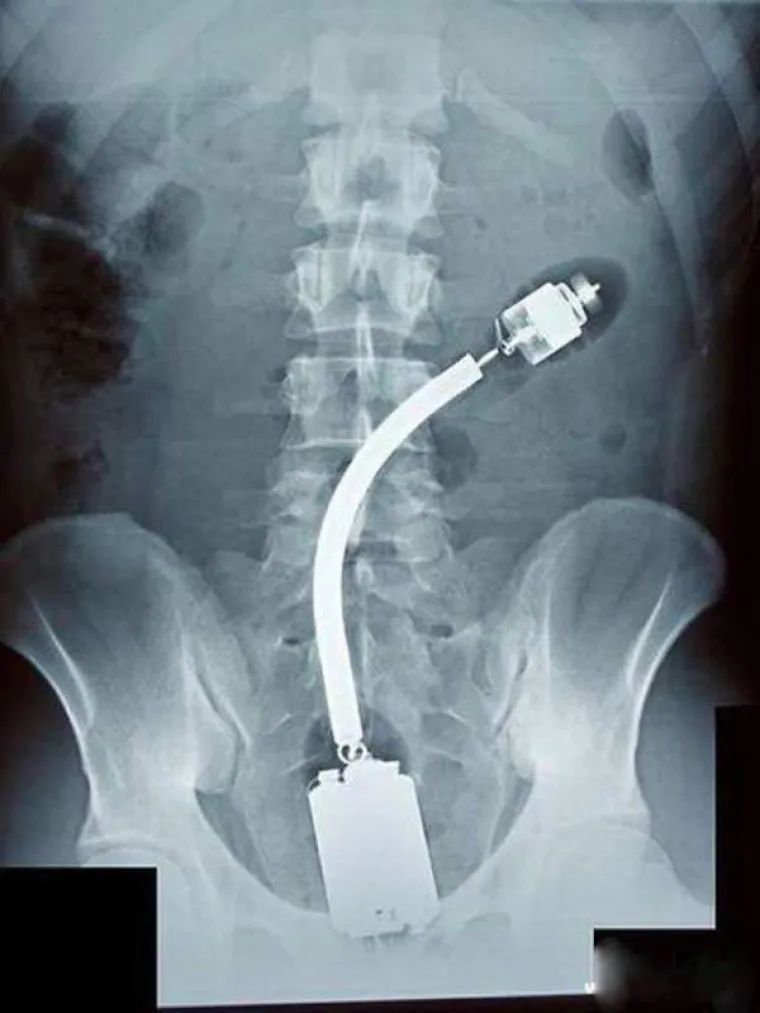

LJUDI SU ČAROBNO SPREMIŠTE, U NJIH STANE BAŠ SVE: Nevjerojatne snimke pokazuju što su sve uspjeli ugurati u sebe

Foto: thechive.com

4 /17